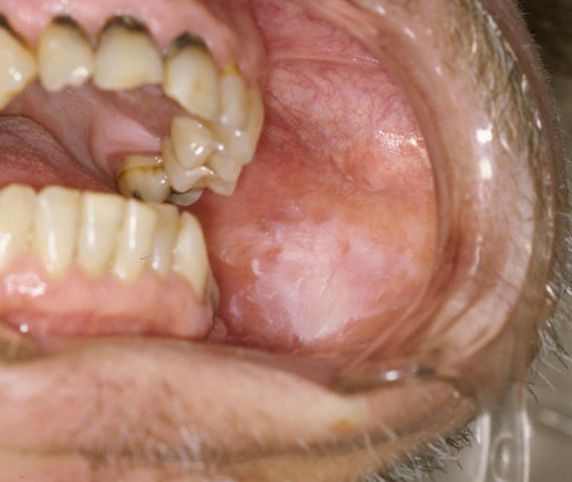

Tobacco Use: The most common cause, including smoking cigarettes, pipes, cigars, or using chewing tobacco. Chronic Irritation: Sharp, broken teeth, or poorly fitting dentures/braces that rub against the cheek or tongue. Alcohol Consumption: Long-term, heavy alcohol use. Immune System Issues: Oral hairy leukoplakia is caused by the Epstein-Barr virus (EBV), primarily occurring in people with HIV/AIDS or other immunosuppression.